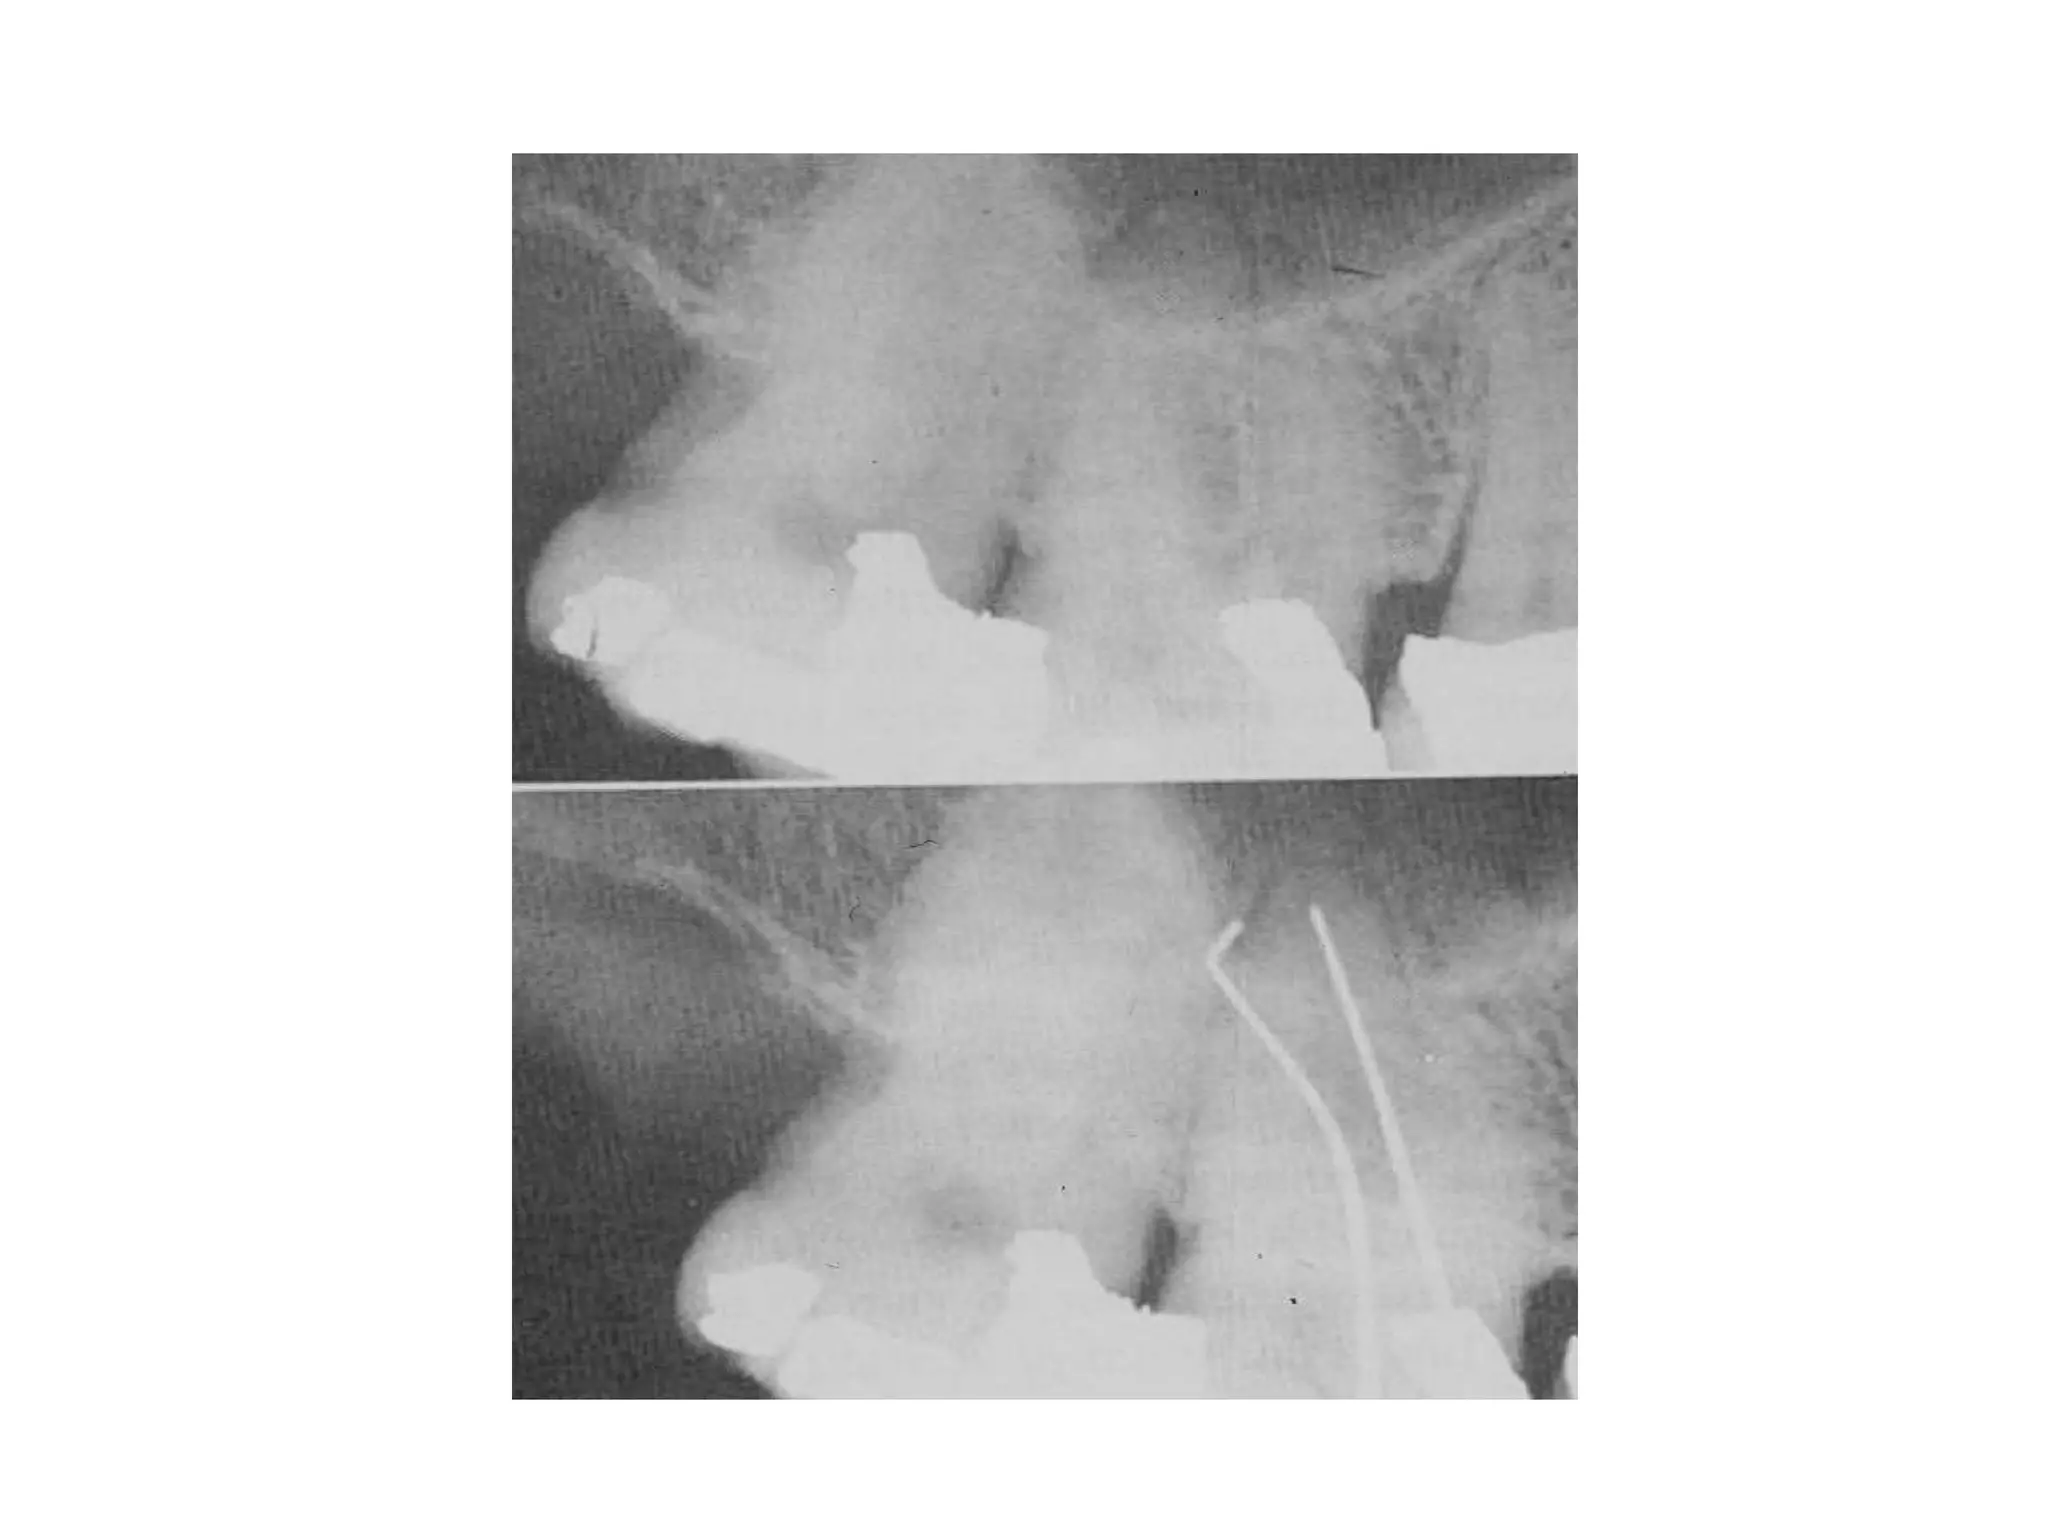

Severe Adult Periodontitis

Tooth mobility

Extensive horizontal bone

loss or vertical osseous

defects

Furcation involvement

Severe adult

periodontitis